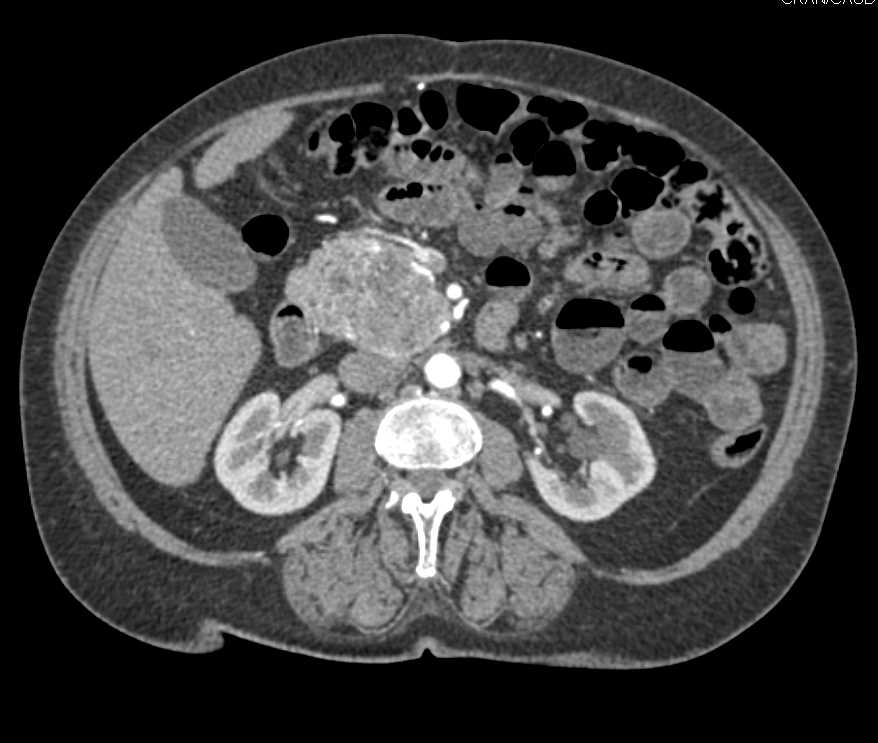

Neuroendocrine Tumor Head of Pancreas